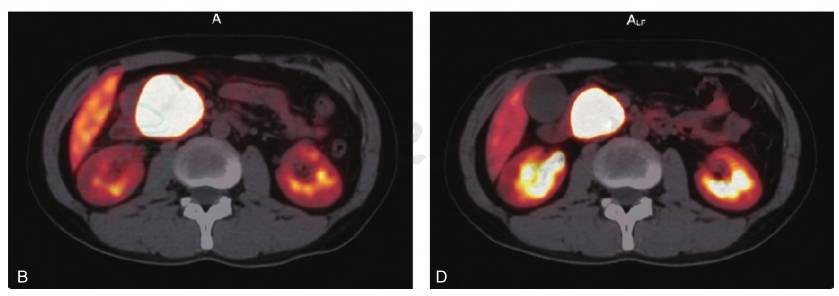

图1 68Ga-DOTA-NOC PET/CT评价(肽受体放射性核素治疗PRRT疗效)

患者,男,25岁。胰腺神经内分泌肿瘤。经过4次PRRT后,肿瘤原发病灶缩小50%,症状基本消失,肿块中央有部分坏死。分别为治疗前CT图(A)、治疗前PET/CT融合图(B)、4次PRRT治疗后CT图(C)和4次PRRT治疗后PET/CT融合图(D)。